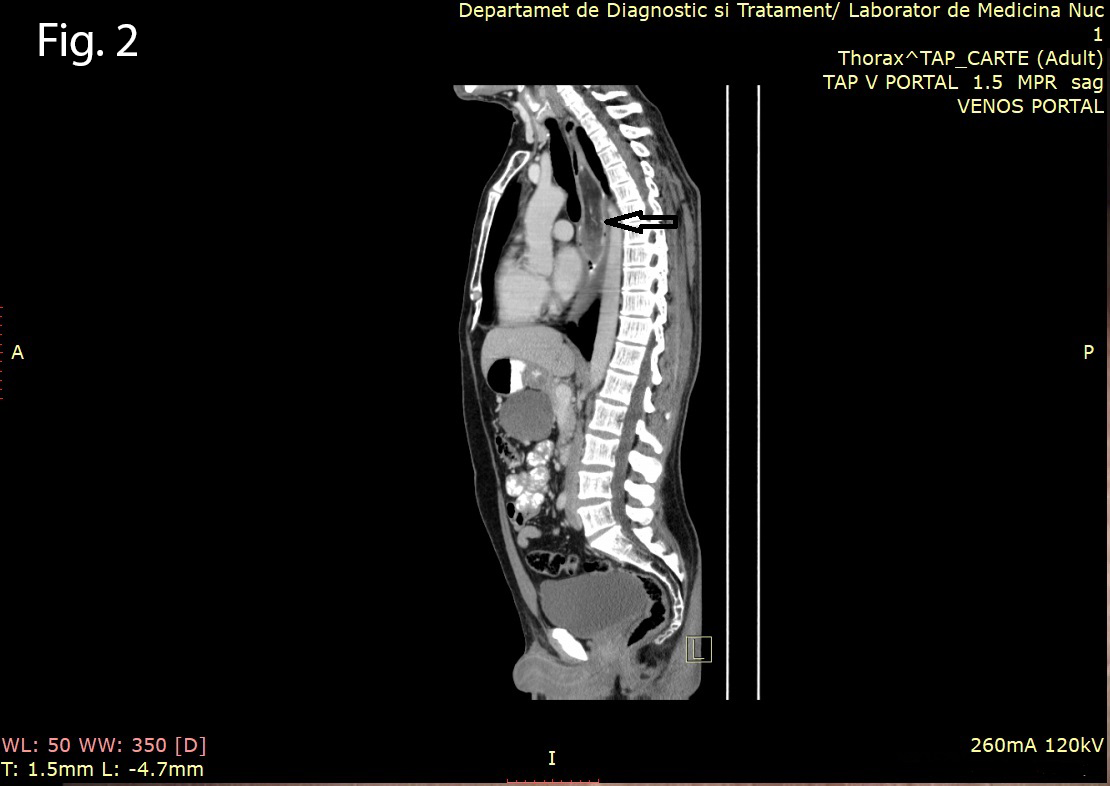

A 46-year old man presented to the gastrointestinal clinic complaining of dysphagia, regurgitation and a sensation of a lump in the throat, symptoms which had progressively worsened over the previous year. Upper GI endoscopy revealed a giant soft mass within the esophageal lumen, with a smooth surface covering, originating from the cervical esophagus, with a positive ”squeeze sign” (Video 1). EUS was performed and showed a giant mobile lesion occupying the esophageal lumen, with hyperechogenic structure, suggestive of a lipoma (Figure 1ab). Contrast-enhanced EUS did not depict any signals inside the subepithelial mass in the early arterial or late venous phases(Figure 1c). In order to define the surgical approach, a CT of the neck, thorax and abdomen was performed and it revealed the submucosal pedunculated tumor mass, confirming the diagnosis of lipoma (Figure 2).

Figure 1a-b. EUS showing a hyperechogenic lesion with a smooth margin arising from the submucosal layer of the esophagus. 1c. Contrast-enhanced EUS indicated completely absent signals, for both the early arterial and late venous phases.

Figure 2. Contrast-enhanced CT showing the characteristic pedunculated lesion suggestive of lipoma (arrow).